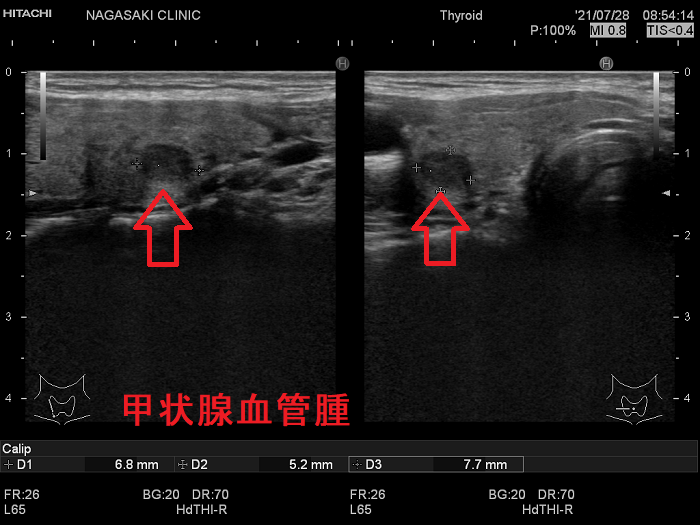

甲状腺に発生する血管腫は非常に稀で、日本の報告例もわずかです(日臨外会誌 72(3),579―583,2011)。

ケース①

ケース②

ケース③

甲状腺血管腫(拡大) ドプラーモード(eFlow);腫瘍内血管が3次元的に見え、毛玉の様。

ケース④